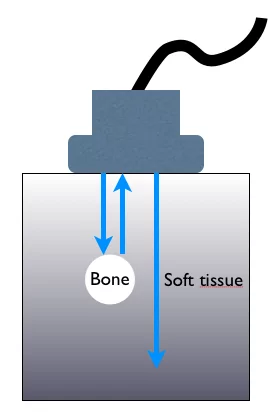

The primary clinical application of ultrasound today is as a diagnostic tool and as a means to display anatomical structures, for which frequencies between 1 and 20 MHz are most commonly used